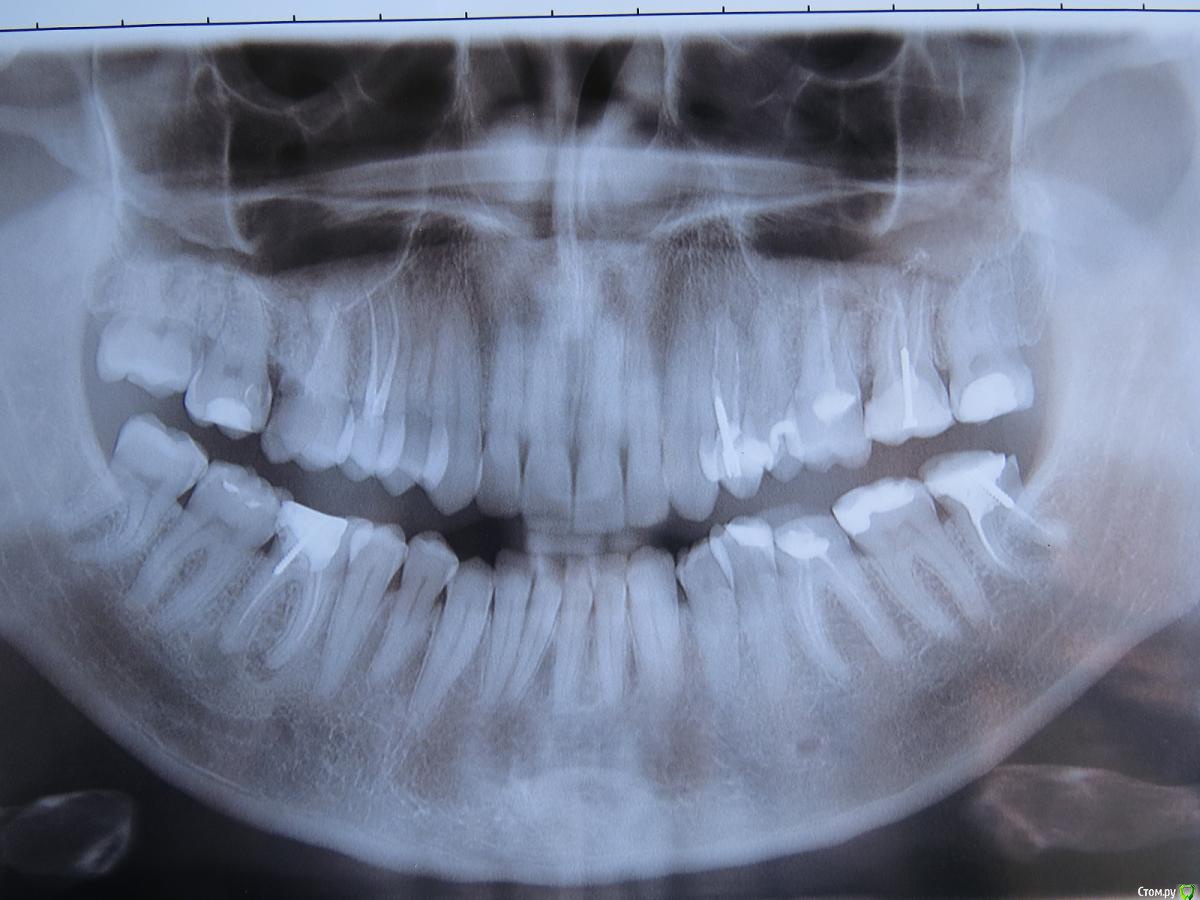

Zaph Опубликовано 21 декабря, 2015 Поделиться Опубликовано 21 декабря, 2015 Здравствуйте! У меня немного скололась стеночка 7-го зуба между 7-м и 8-м (снизу слева). Туда стала забиваться пища, из-за этого воспалена десна.Я пришел к врачу, она мне сказала, что скол очень незначительный и рушить реставрацию 7-го зуба для восстановления межзубного пункта она бы не стала. Лучше что-то решать с восьмеркой, там старая пломба и под ней начинается кариес. Но если ее лечить, то надо ставить коронку. Пошел к ортопеду в этой же клинике, результат - поставить коронку не сможем, так как малая операционная высота.Действительно коронка зуба достаточно низкая, скорее всего была еще дополнительно спилена в ходе лечения. Щечная стенка 1мм от края десны, язычная 3 мм. Но, если посмотреть на снимок, то видно что сама коронка достаточно высока, просто скрыта под десной. Может быть, сделать гингивэктомию, получить достаточную операционную высоту и запротезировать, используя штифтовую вкладку, например? Конечно, это мои дилетантские размышления, но очень бы не хотелось терять восьмерки на левой стороне. Жуют они сейчас очень хорошо, перетирают пищу лучше семерок. Поделитесь, пожалуйста, возможным планом лечения. Ссылка на комментарий

Zaph Опубликовано 21 декабря, 2015 Автор Поделиться Опубликовано 21 декабря, 2015 Мудрые зубы удаляйте, для начала слева.Вам терапевт и ортопед но ОПГ больше ничего не сказали?Сейчас прохожу эндо на 6-х, там гранулемы если вы об этом. Или там еще что-то есть на что обратить внимание?А зубы мудрые все-же не хотелось бы удалять, что думаете по поводу убрать десну и запротезировать? Ссылка на комментарий

chervoncevdaniil Опубликовано 21 декабря, 2015 Поделиться Опубликовано 21 декабря, 2015 (изменено) Сложно что то советовать,не видя ситуации во рту.Чтобы коронка держалась на зубе нужно минимум 4-5 мм самого зуба плюс толщина материала из которого будет сделана коронка,иначе это будут либо расцементировки,либо ее просто нереально изготовить технически.По рентгену сложно оценить сколько там есть места по прикусу Изменено 21 декабря, 2015 пользователем chervoncevdaniil Ссылка на комментарий

red_butler Опубликовано 21 декабря, 2015 Поделиться Опубликовано 21 декабря, 2015 Если хотите сохранить во что бы то не стало, то можно. Проведут удлинение клинической коронки, перелечат каналы, ортодонтия.НО у Вас и без восьмых зубов работы во рту непочатый край. Вот на это и тратьте время, силы и средства Ссылка на комментарий

Zaph Опубликовано 21 декабря, 2015 Автор Поделиться Опубликовано 21 декабря, 2015 Сложно что то советовать,не видя ситуации во рту.Чтобы коронка держалась на зубе нужно минимум 4-5 мм самого зуба плюс толщина материала из которого будет сделана коронка,иначе это будут либо расцементировки,либо ее просто нереально изготовить технически.По рентгену сложно оценить сколько там есть места по прикусуНу да 4-5 мм это солидно, может столько и не будет у меня до кости. После НГ схожу в другую клинику, посмотрю, что скажут... Ссылка на комментарий